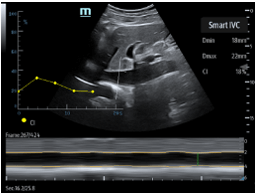

Smart Inferior Vena Cava (Smart IVC) – Automated measurement of Inferior Vena Cava (IVC) helps assess volume status and guides fluid management. A trending graph documents the change in collapsibility (CI) and distensibility (DI) to document fluid response over time and guide therapy.

Smart Inferior Vena Cava (Smart IVC) – Automated measurement of Inferior Vena Cava (IVC) helps assess volume status and guides fluid management. A trending graph documents the change in collapsibility (CI) and distensibility (DI) to document fluid response over time and guide therapy.